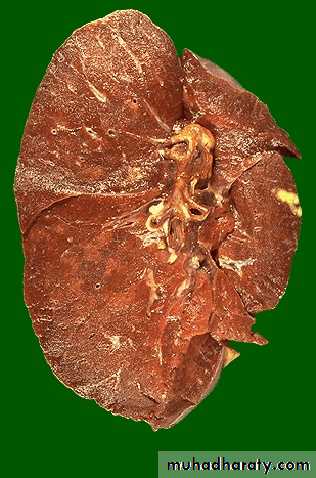

usually occurs at the apex of the lung with minimal lymph node involvement. There is marked damage in the lung parenchyma with cavity formation